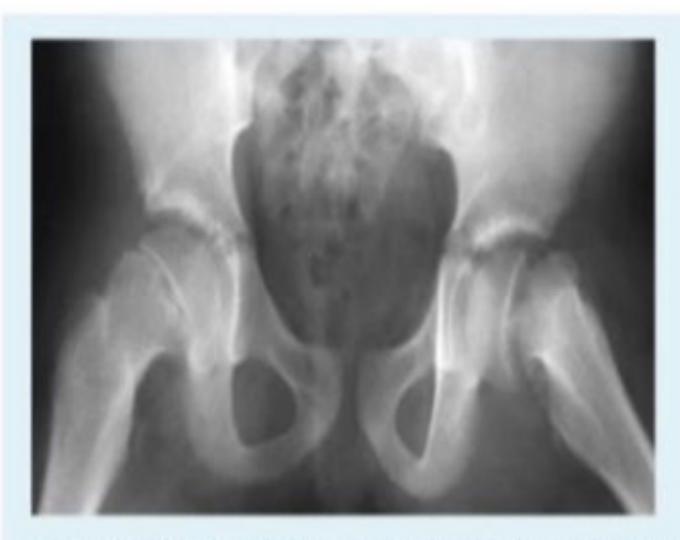

Developmental Dysplasia of the Hip (DDH)

Radiological Findings

What are the four main radiological findings in DDH?

- Acetabular index more than 25ยฐ

- Broken Shentonโs line

- Smaller size of femoral head ossification center

- Lateralization of femoral head to perpendicular line

A case scenario that was suggestive of developmental dysplasia of the hip in an 18-month-old girl. Which of the following radiological signs represents this case?

Clinical Cases

A 15-month-old child was brought to the clinic because of painless limping. There is no history of trauma. The pelvic x-ray is shown.

Q1: Write two abnormalities seen on the X-ray.

- Lateralization of the ossifying centre

- Acetabular angle more than 27ยฐ

- Broken Shenton line

- Shortening of the line from greater trochanter to the horizontal line

Q2: What is the most probable diagnosis?

- Developmental dysplasia of the hip (DDH)

10 months old child presenting with this condition:

- Right DDH